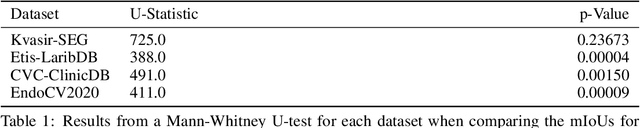

Abstract:Generalizability is seen as one of the major challenges in deep learning, in particular in the domain of medical imaging, where a change of hospital or in imaging routines can lead to a complete failure of a model. To tackle this, we introduce Consistency Training, a training procedure and alternative to data augmentation based on maximizing models' prediction consistency across augmented and unaugmented data in order to facilitate better out-of-distribution generalization. To this end, we develop a novel region-based segmentation loss function called Segmentation Inconsistency Loss (SIL), which considers the differences between pairs of augmented and unaugmented predictions and labels. We demonstrate that Consistency Training outperforms conventional data augmentation on several out-of-distribution datasets on polyp segmentation, a popular medical task.